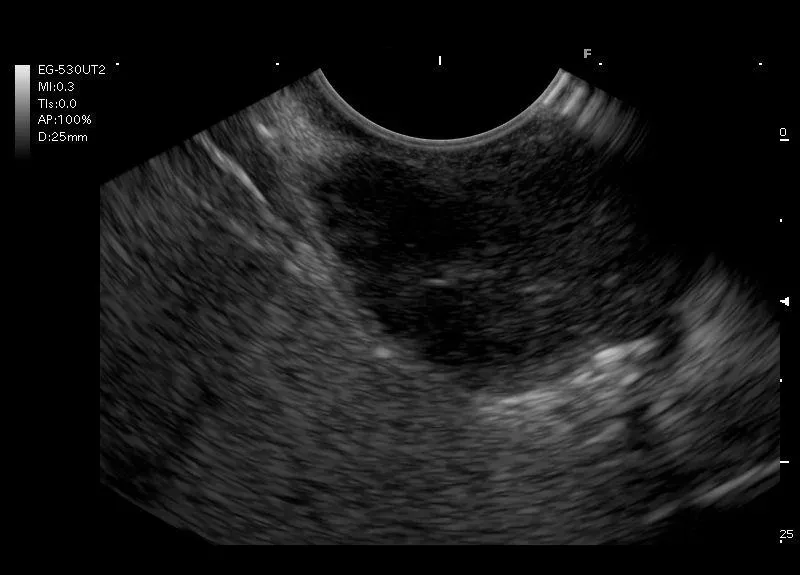

W większej części hypoechogeniczna, heterogenna, owalna zmiana, widoczna w ścianie żołądka mogąca odpowiadać trzustce ektopowej